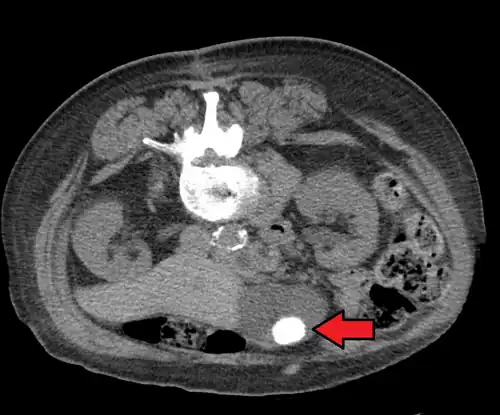

Gallstones as seen on plain X-ray

Large gallstone as seen on CT -